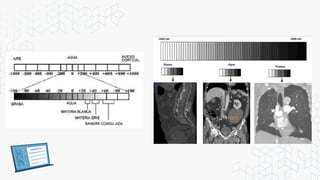

ESCALA DE GRISES CON LAS UNIDADES

Existe una escala de densidades tomográficas conocida como

la escala de Unidades Hounsfield (UH), la cual es básicamente

una escala de grises. En esta escala se asigna un valor

numérico a las densidades y va desde -1000UH (Muy negro =

aire), 0UH (Densidad de agua), y +1000UH (Muy blanco =

metal).

Es el número asignado a cada pixel en la

imagen final de una tomografía

computarizada. (TC) y es la expresión de la

densidad del objeto irradiado.

En honor al inventor Godfrey Hounsfields

Rango desde -1000 a +1000

Negativos de -100 grasa

Más negativos -1000 aire

500 a 800 densidad osea.

Unidades de Hounsfield